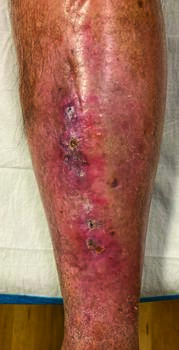

The orthopedist providing an additional opinion ordered radiographs, which showed multiple soft tissue calcifications along the anterior tibia and fibula with no evidence of cortical disruption (see second photo above). At this point, the orthopedist deferred further treatment to infectious disease, who attempted a six-week regimen of culture-driven IV antibiotics.